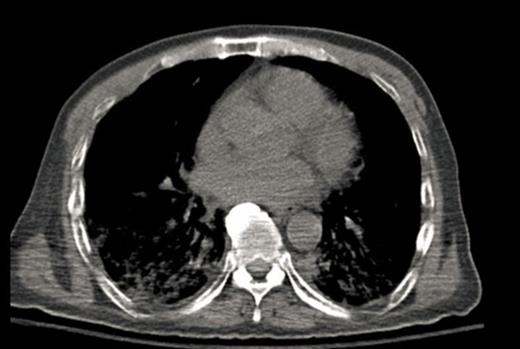

A 64-year-old male with chronic low back pain presented to the emergency department with new onset severe mid back pain radiating to bilateral shoulders. CT scan, performed to rule out aortic dissection, demonstrated multiple lytic lesions throughout the bony skeleton and a compression fracture at T7 vertebral body with epidural extension of soft tissue. A bone survey confirmed CT scan findings, and subsequent bone marrow biopsy confirmed the diagnosis of MM. He received radiation therapy to the thoracic spine and completed 2 cycles of CyBorD regimen (Cyclophosphamide 300 mg/m2 by mouth, BTZ 1.5 mg/m2 sub-cutaneous, and Dexamethasone 40 mg by mouth each on day 1, 8, 15 and 22). Three days after the completion of the second cycle, he was admitted to hospital with respiratory distress. CT chest (Image 2) showed new interval appearance of bilateral perihilar groundglass opacities, peribronchial and interstitial thickening predominantly in the upper lobes not seen in prior scan (Image 1). There were no other signs or symptoms of pneumonia such as leukocytosis, fever or cough. After some benefit from oral prednisone, he was discharged with a tapering dose of the same. Unfortunately, patient was readmitted with worsening respiratory distress 4 days later. A repeat CT scan of the chest showed resolution of previously well-defined areas of perihilar ground glass opacities but development of hazy areas of ground-glass opacification throughout both lungs with more confluent abnormalities in bilateral lower lobes (Image 3). Patient was treated with high dose methyl-prednisone and noninvasive positive pressure ventilation without any improvement. Family requested do-not-resuscitate and do-not-intubate status. Patient died on 10th day of the admission.